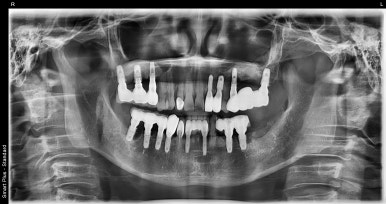

오른쪽 위(실제로는 왼쪽) 앞니 임플란트 전후 비교

(전) 2023-01-09 (후) 2023-08-18

이 환자분 역시 최초 수술부터 임플란트 보철물 완전 부착까지 약 7개월 정도 소요되었습니다.

그동안 혹시 앞니없이 살아야되는거 아닌지 걱정되실 것 같은데요. 그건 걱정하지 않으셔도 됩니다.

오랜 기간동안 앞니가 없으면 불편한 점이 한 두가지가 아니기 때문에 앞니임플란트를 하게 되시면 저희가 임시치아를 만들어드립니다.

물론 말 그대로 임시로 쓰는 치아이기 때문에 무언가를 씹어먹거나 하는데는 불편한 점이 있습니다만

육안으로 보이기에 비어있는 공간이 없이 채워주는 느낌이라고 보시면 됩니다.

이런 앞니임플란트는 어금니임플란트와 동일한 비용을 책정하고 있는데요.

저희 디데이치과를 기준으로 개당 69~79만원정도의 비용이 발생하며, 오실 때마다 그 때 그 때 진료비용이 조금씩 나올 수 있습니다.

만약 뼈이식이 추가된다면 개당 비용은 30만원정도 추가됩니다.